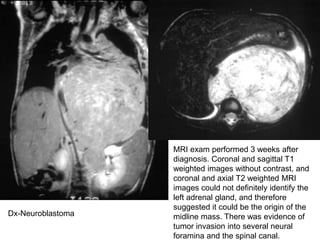

MRI exam performed 3 weeks after

diagnosis. Coronal and sagittal T1

weighted images without contrast, and

coronal and axial T2 weighted MRI

images could not definitely identify the

left adrenal gland, and therefore

suggested it could be the origin of the

midline mass. There was evidence of

tumor invasion into several neural

foramina and the spinal canal.

Dx-Neuroblastoma